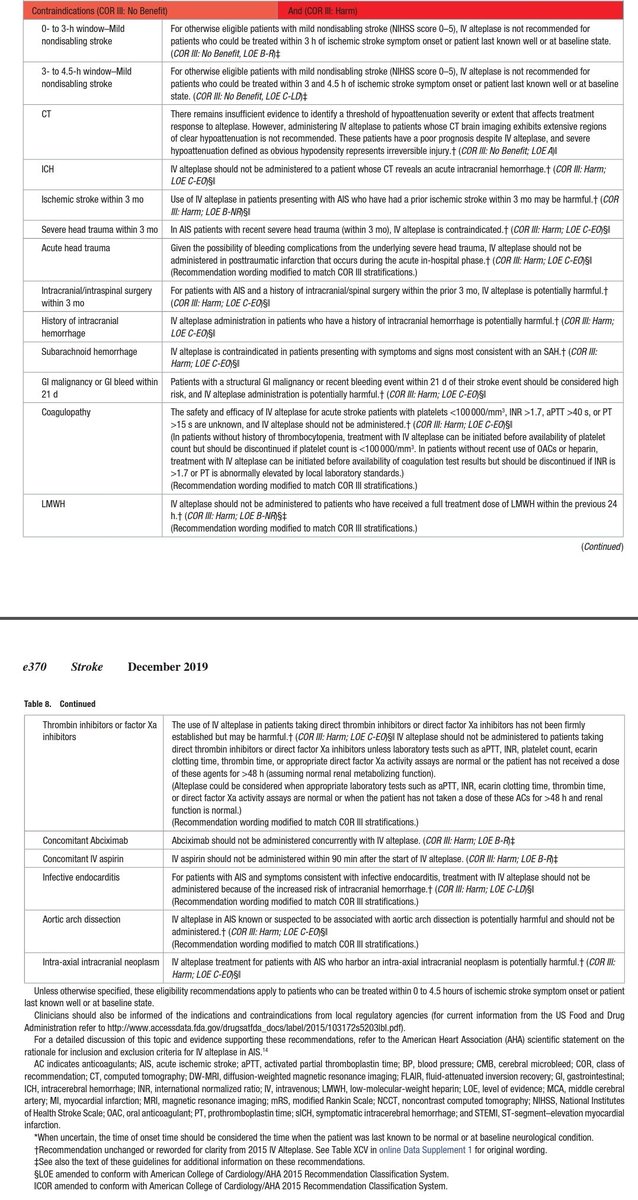

💥متى نتجنب المذيب

🧠التأخر عن٤ ساعات ونصف

🧠ظهور دلائل موت الخلايا بالاشعات

🧠عمليات المخ أو الحبل الشوكي أوخبطات الراس

🧠جلطات القلب

🧠وجود نزيف

🧠علاجات السيوله القويه

🧠تشوهات الاوعيه بالمخ

🧠أورام المخ

🧠نقص الصفائح الدموية

🧠التهاب صمامات القلب

💥متى نتجنب المذيب

🧠التأخر عن٤ ساعات ونصف

🧠ظهور دلائل موت الخلايا بالاشعات

🧠عمليات المخ أو الحبل الشوكي أوخبطات الراس

🧠جلطات القلب

🧠وجود نزيف

🧠علاجات السيوله القويه

🧠تشوهات الاوعيه بالمخ

🧠أورام المخ

🧠نقص الصفائح الدموية

🧠التهاب صمامات القلب

للاطباء المهتمين في علاج السكتات الدماغيه الحاده

Latest 2019 guidelines for acute stroke

ahajournals.org

Other recommendations attached 👇👇